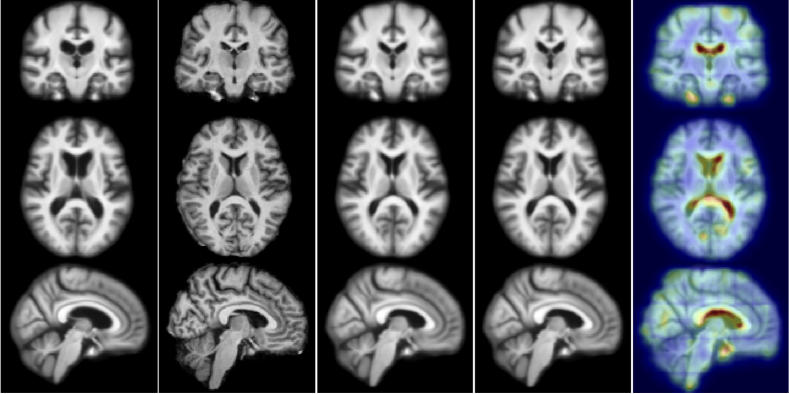

Figure 2: Test example for 2D (top) and 3D (bottom). From left to right: moving (atlas) image, target image, deformation result by optimizing LDDMM energy, deformation result using 50 samples from probabilistic network with a stride of 14 and patch pruning, and uncertainty as square root of the sum of the variances of deformation in all directions mapped on the predicted registration result. The colors indicates the amount of uncertainty (red = high uncertainty, blue = low uncertainty). Best viewed in color.

2D Data. For the 2D experiment, we compare our method with semi-coupled dictionary learning (SCDL), which was used to predict initial momenta for LDDMM in [2]. To compare the deformation prediction accuracy using different parameterizations, we trained (i) networks predicting the initial velocity, v0=Km0subscript𝑣0𝐾subscript𝑚0v_{0}=Km_{0}, and the displacement field, Φ(1)idΦ1id\Phi(1)-\operatorname{id}, of LDDMM, respectively. For the initial momentum and the initial velocity parameterizations, the resulting deformation map Φ(1)Φ1\Phi(1) was computed by integrating Eqs. (2). We quantify the deformation errors as the pixel-wise 2-norm of the deformation error with respect to the ground-truth deformation obtained by PyCA LDDMM. Table 1 shows the error percentiles over all pixel and test cases. We observe that our initial momentum networks significantly outperform SCDL and also improve prediction accuracy compared to the initial velocity and the displacement parameterizations in both the 1-stride and the 14-stride ++ patch pruning cases. In contrast to the initial velocity and the displacement parameterizations, both our deterministic and our probabilistic networks show comparatively small sensitivity to patch pruning and stride, validating our hypothesis that the momentum-based LDDMM parameterization is well-suited for fast predictive image registration. One of the hallmarks of LDDMM registration is that given a sufficiently strong regularization, the obtained deformation maps, Φ(1)Φ1\Phi(1), will be diffeomorphic. To assess this property, we computed the local Jacobians of the deformation maps. Assuming no coordinate system flips, a diffeomorphic Φ(1)Φ1\Phi(1) should have a positive definite Jacobian everywhere, otherwise undesirable foldings exist. Column ‘detJ>0det𝐽0\text{{det}}J>0’ of Table 1 lists the percentage of test cases with positive definite Jacobian, revealing that our initial-momentum based networks retain this property in all scenarios, even for very large strides and patch pruning. Direct displacement prediction, however, cannot even guarantee diffeomorphic transformations for a stride of 1 (which includes a lot of local averaging) for all our test cases and results in no diffeomorphic transformations at a stride of 14. Velocity prediction performs slightly better, but can also not guarantee diffeomorphic maps at large strides. Similarly to existing optical flow prediction methods [16, 4], a direct prediction of displacements or velocities cannot encode smoothness assumptions or enforce transformation guarantees. Our momentum parameterization encodes these assumptions by design. Fig. 2 shows an example of our 2D deformation prediction with uncertainty. The predicted deformation is close to the one generated by costly LDDMM optimization. The uncertainty map shows high uncertainty at the anterior edge of the ventricle and the posterior brain cortex where drastic shape changes occur, which can be seen in the moving and the target image.

3D Data. Similar to the 2D case, we computed the deformation error for every voxel in all test cases; results are listed in Table 1. Our networks achieve sub-voxel accuracy for about 99.8% of all the voxels. Fig. 2 shows one 3D registration result using the predicted deformation from our probabilistic 3D network using the mean of 50 initial momentum samples, as well as the uncertainty of the deformation field. Our prediction is able to handle large deformations. As in 2D, the uncertainty map highlights areas with drastic and ambiguous deformations.